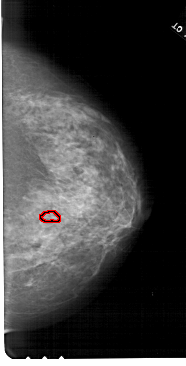

A_1664_1.RIGHT_CC

RIGHT_CC LINES 6586 PIXELS_PER_LINE 3346 BITS_PER_PIXEL 12 RESOLUTION 43.5 OVERLAY

FILE: A_1664_1.RIGHT_CC.OVERLAY

TOTAL_ABNORMALITIES 1

ABNORMALITY 1

LESION_TYPE CALCIFICATION TYPE PLEOMORPHIC DISTRIBUTION LINEAR

ASSESSMENT 4

SUBTLETY 2

PATHOLOGY MALIGNANT

TOTAL_OUTLINES 1

BOUNDARY